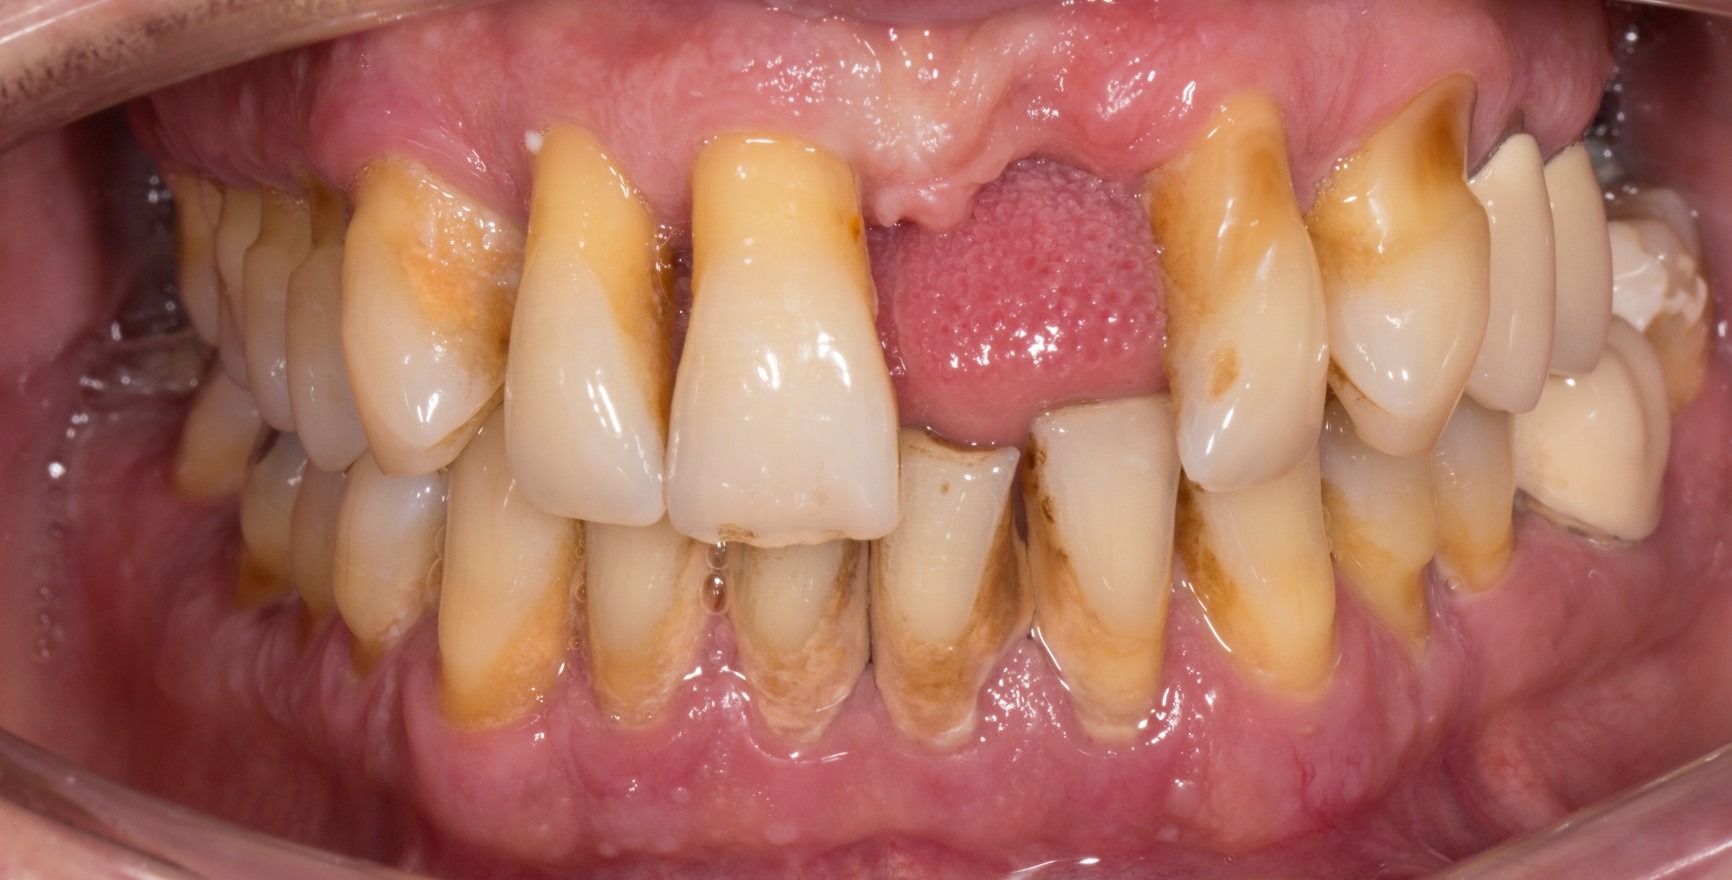

A state of clinical periodontal health in the intact periodontium is distinguished from that in a reduced periodontium already affected by clinical loss of attachment. This loss of attachment can occur:

as result of inflammation during the course of periodontitis. Clinical periodontal health then describes a stable condition after successful completion of periodontal treatment.

The clinical criterion is always the absence of bleeding on careful probing (bleeding on probing = BoP). A distinction is made between a site/tooth-specific diagnosis with a negative BoP finding at the corresponding measurement site, and diagnosis on the level of the tooth or patient, for which a threshold value of a BoP ≤ 10% still meets the criteria of clinical periodontal health. Pocket probing depths must be no more than 3 mm. In a reduced periodontium after periodontal treatment, a threshold value of 4 mm is still regarded as a stable status (Matuliene et al., 2008).

If a diagnosis of ‘clinical periodontal health’ is made, the patient’s history must be taken into account to ensure their correct future care: periodontitis is a chronic disease that can be successfully controlled by means of treatment. Unlike for fully reversible gingivitis, however, even if the patient has a stable condition after periodontitis treatment, they are nonetheless at an increased risk of further loss of attachment. The periodontitis patient will remain a periodontitis patient for the rest of their life and will therefore need long-term periodontal maintenance therapy (PMT).